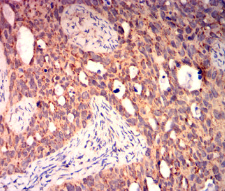

BAX Mouse Monoclonal antibody[6H8E1]

IHC    1/200-1/1000